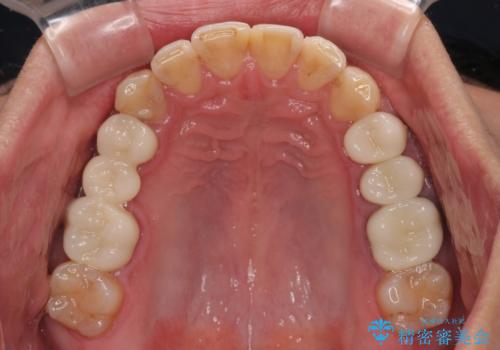

銀歯を白くしたい 一緒に矯正治療も行ない美しい口腔内に

- 近医にて下顎奥歯の抜歯が必要と言われたとのことで来院された患者様です。

診察の結果、奥歯は左右ともに抜歯が必要な状態でした。

他の銀歯も気になっており、セラミックにしたいとの要望があり、詳しくお話をすると、デコボコの歯ならびも整えたいとのことでした。

抜歯が必要な歯は事前に抜歯をし、その後ワイヤー装置にて歯列矯正を行い、途中でインプラントを埋入し、オールセラミッククラウンにて補綴治療を行うこととしました。

矯正治療にやや時間がかかりましたが、歯列はきれいに整い、気になっていたむし歯や銀歯は自然な色合いに仕上がりました。